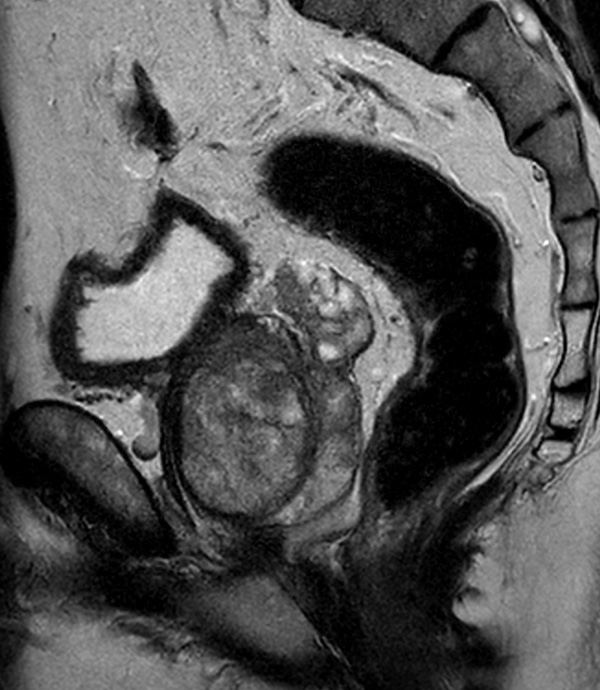

A 60-year-old male with elevated PSA and weak urinary stream underwent MRI. The exam includes high resolution DWI and ADC mapping as well as dynamic imaging. The prostate gland measures 5.2 x 4.4 x 5.9 cm in maximal transverse, AP, and craniocaudal dimensions, respectively, corresponding to an approximate glandular volume of 70 ml. Heterogeneous nodular hypertrophy is seen along the central transitional zone, with hypointense pseudo capsule, indicative of BPH, without dominant T2-hypointense nodules. Patchy T2-hypointense foci are noted throughout the peripheral zone bilaterally at the base, mid-gland and apex, with total PI-RADS score 6, so probably benign. No dominant nodular areas of restricted diffusion are evident. A geographic T2-hyperintense focus in the peripheral zone at the right base to mid-gland, paramidline shows asymmetric restricted diffusion, total PI-RADS score 10. No dominant lesions, greater than 1 cm. Clinical correlation and follow-up are advised.